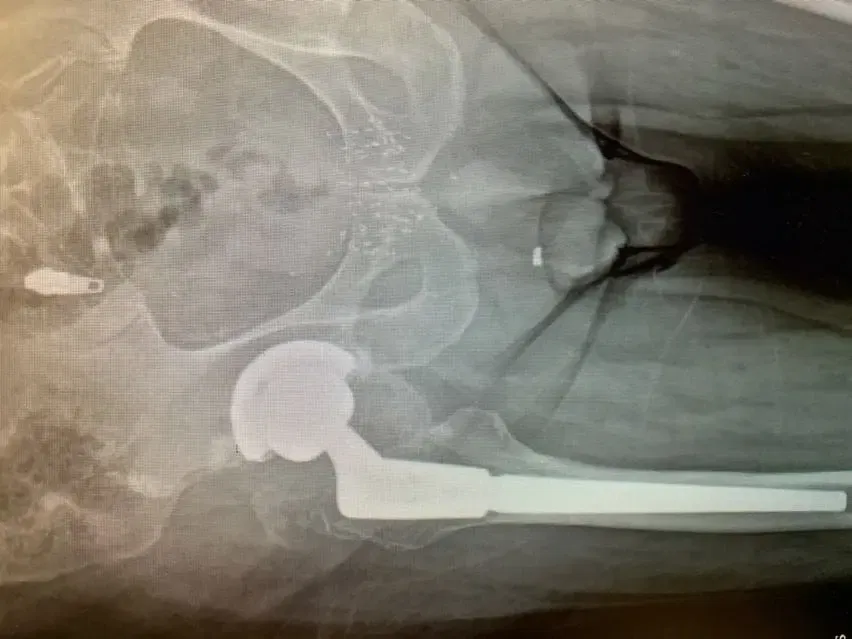

Retiramos con cuidado el componente femoral y el revestimiento de plástico del componente acetabular; las pruebas de la carcasa metálica revelaron que era estable, por lo que se decidió que esta parte de la intervención original permanecería intacta. Preparamos e insertamos el componente femoral de revisión sin eventos y probamos componentes de cabeza femoral con componentes de revestimiento acetabular de prueba para asegurarnos de que la cadera permanecía estable. Una vez que estuvimos satisfechos con los tamaños de nuestros componentes, se colocaron los componentes definitivos y se completó el procedimiento.

6 semanas después de la operación, el Sr. JF había recuperado la mayor parte de su fuerza, había vuelto a su estado anterior sin dolor y hasta la fecha no ha tenido ningún episodio recurrente ni sensación de inestabilidad.